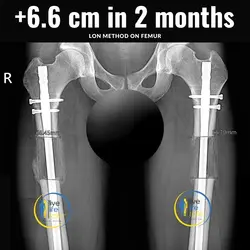

With the combined method (Lon method), an internal nail and an external fixation are attached which allow the bone to be extended from the outside.